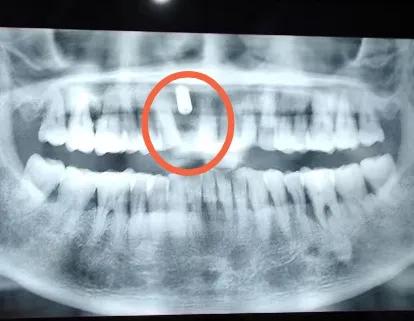

钱就是该花在有意义的事情上,给爸妈治疗牙齿肯定算一件。然后我就全城找给老妈看牙的诊所。以下是我妈的牙片记录:

一共有两处损坏

右侧拔出一颗牙齿后,空缺处容易积累食物残渣导致蛀牙,损坏了牙齿表面需要进行补牙或者根管治疗装牙冠。